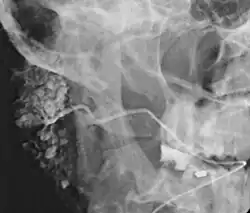

Sialogram in a patient suspected of Sjögren's syndrome

This procedure is indicated when there is recurrent swelling and pain on the face but ultrasound has not revealed any problems. If Sjögren syndrome (also known as Sicca syndrome, an autoimmune disease that affects the lacrimal and salivary glands, causing reduced tears and saliva production) is suspected, this procedure is useful. Besides, when interventional procedure is planned such as stone removal from salivary ducts or dilatation of the strictures in the salivary gland, this procedure is also indicated.[4] However, for those who are pregnant, with allergy to iodinated contrast, and ongoing infection or inflammation of the face, the procedure is contraindicated.[4]

This study is interpreted by evaluating the morphology of the salivary ducts for obstructions and chronic inflammation. Sialodochitis is a term describing dilation of the ducts caused by repeated inflammatory or infective processes. There is also irregular salivary duct stricture (narrowing) of the duct, which creates an appearance known as "sausage link" pattern on a sialogram. Suggestions of abscesses and autoimmune diseases such as Sjögren syndrome can also be elicited. Sialadenitis is inflammation of the salivary glands, which may cause acinar atrophy and create an appearance known as "pruning of the tree" on a sialogram, where there are less branches visible from the duct system. A space occupying lesion that occurs within or adjacent to a salivary gland can displace the normal anatomy of the gland. This may create an appearance known as "ball in hand" on an sialogram, where the ducts are curved around the mass of the lesion.[6]